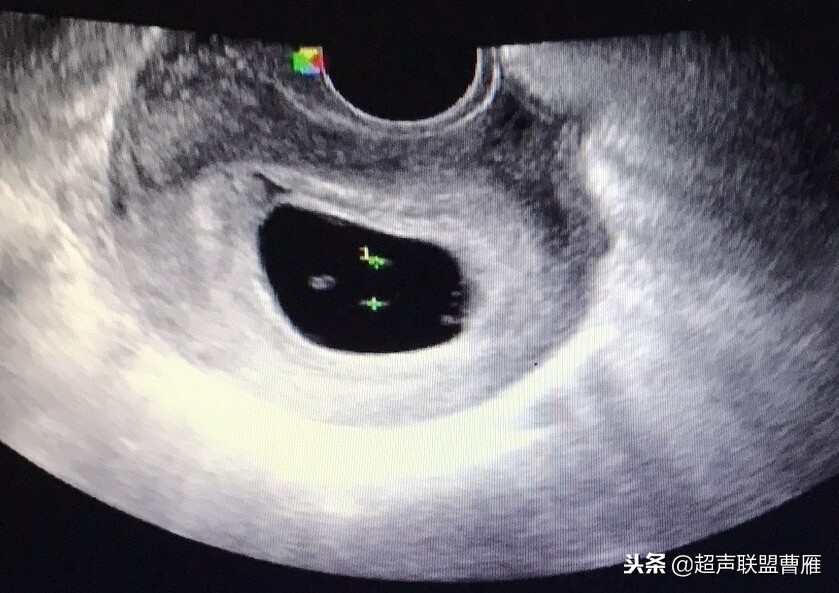

一个孕囊有两个卵黄囊,单卵双胎。

两个孕囊各有一个卵黄囊,双卵双胎,HCG应该更高。